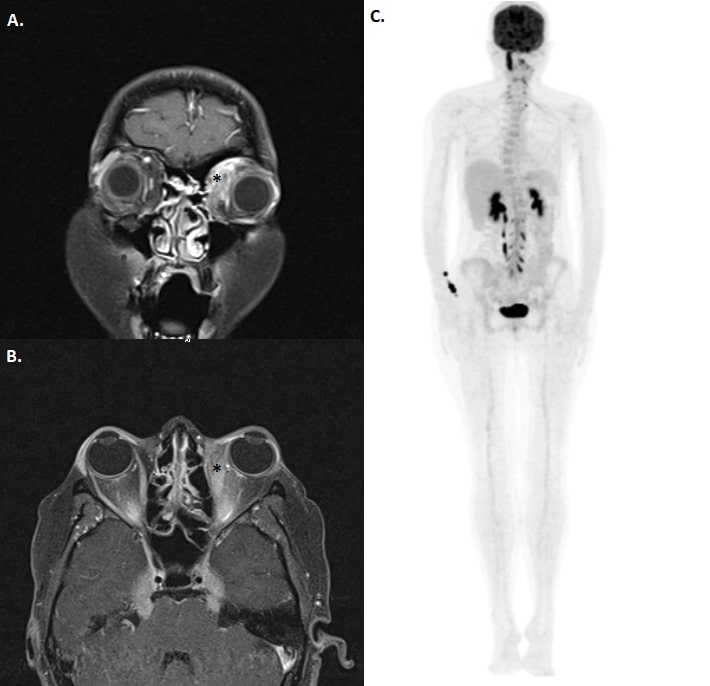

Repeated orbital magnetic resonance scanning with T1 fat suppression sections showed increased contrast retention in left medial orbital soft tissue (Figure 3A [Fig. 3]) and left medial rectus muscle (Figure 3B [Fig. 3]). Positron emission tomography (PET) scan was performed and increased fluorodeoxyglucose (FDG) uptake was seen in hypopituitary gland, left orbital medial region, right wrist, nasal septum, upper dorsal and lumbar vertebral and sacral region (Figure 3C [Fig. 3]). Anti-tuberculosis treatment was stopped due to disease progression under treatment and orbital biopsy was planned.

Figure 3: In coronal and axial T1 fat suppression MRI sections, increased contrast retention in left medial rectus and medial orbital soft tissue were observed (right). Increased FDG intake in right wrist, dorsal, lumbar and sacral vertebras was observed at PET-CT (left).